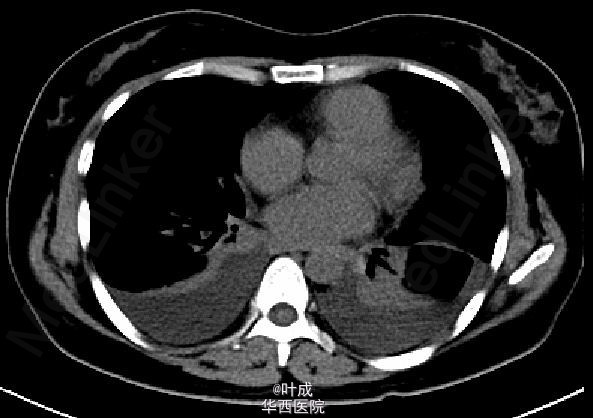

患者女,40岁,因“反复腹痛5+年,复发加重1+天”入院。急诊查血清AMS 2349 IU/L、 LIP 6647 IU/L,腹部CT平扫示胰腺肿胀,胰周渗出,腹膜炎征象。下为起病四天后复查增强CT影像。